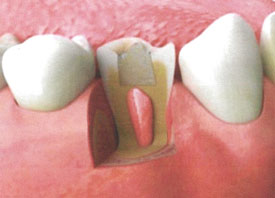

Any time the pulp of a tooth has been injured or irritated, there is a possibility that it may become swollen and painful. This inflammation is called pulpitis. Treating the condition will relieve dis....